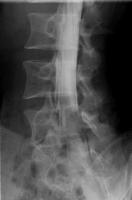

ミエログラフィー

背中に針を刺して、神経が通っている硬膜管内に造影剤を注入し、脊柱管の形状や障害を調べる検査です。

姿勢を変えたときの脊柱管の変化も見ることができるので、手術による治療計画を立てる際に役に立ちます。

ミエログラフィー後にCT検査を追加することで、より詳細に脊柱管の状態を見ることができます。